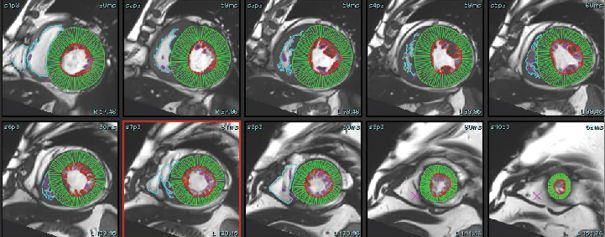

The cine-CMR images were analyzed during routine clinical workflow by using commercial software (syngo.Via). Using the short-axis cine images, the LV and RV end-diastolic and end-systolic frames were identified. In each short-axis slice, the endocardial boundary of the LV and RV were manually delineated. LV and RV papillary muscles and trabecular tissue were included in the blood pool volume. In the LV basal slices, the LV contour was drawn to include the LV outflow tract to the level of the aortic valve cusps (see Figure 1). Contours for the postprocessing of flow study at the level of ascending aorta were drawn by using the manual method, whereas the DL method automatically recognized the aorta, and a contour was formed for all phases (see Figure 2). Simpson’s method of disks was used to calculate the LV Ejection fraction, as well as end-diastolic and end-systolic volumes (EF, EDV and ESV). These values were then reported and recorded. We divided the patient cohort into three clinically relevant groups: severely reduced LVEF (≥ 35%), mildly to moderately reduced LVEF (35–50%), and normal LVEF (≥ 50%). MR was classified as Mild (< 30ml), Moderate grade II (30–44ml), Moderate Grade III (45–59ml), and severe (> 60ml) for SW1, SW2, and echocardiography.

The DL-EF, SV, EDV values were determined from cine short-axis images by using fully automated commercially available algorithms: SuiteHeart, Neosoft, Pewaukee, Wisconsin, USA. The vendor provided virtual training of how to optimally use the software. A single user was trained to use both software packages. Fully automated segmentation was then performed without any user input. The automatically and manually generated LVEDV, LVESV, AoF (Aortic forward flow), PG (Pressure gradient at LVOT) and LVEF were recorded (see Figure 3: A, B, C).